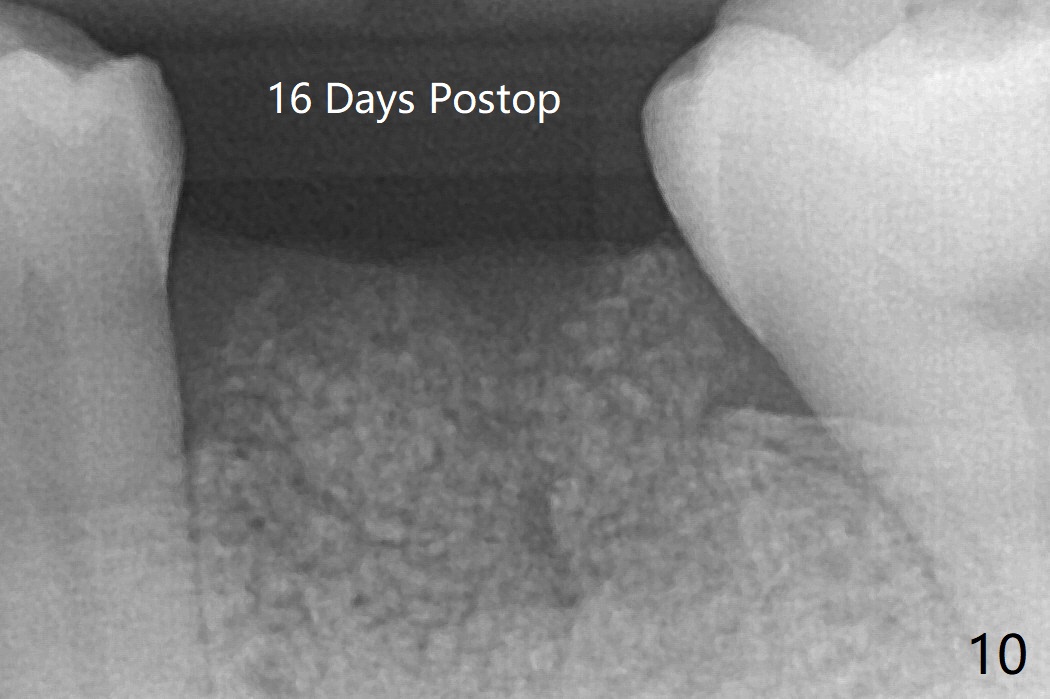

In spite of no apparent loss of bone graft (Fig.4,10), the graft seems to shrink in height 3.5 months postop (Fig.11), while the crest decreases (compare Fig.1 and 11).53岁男左下6因近中根周围阴影(图一)拔除植骨(图四)。术后16天骨粉好像没有失去(图十),但是术后3.5月骨粉仿佛收缩(图十一),牙槽嵴接近牙槽窝处下降(比较所有图)。